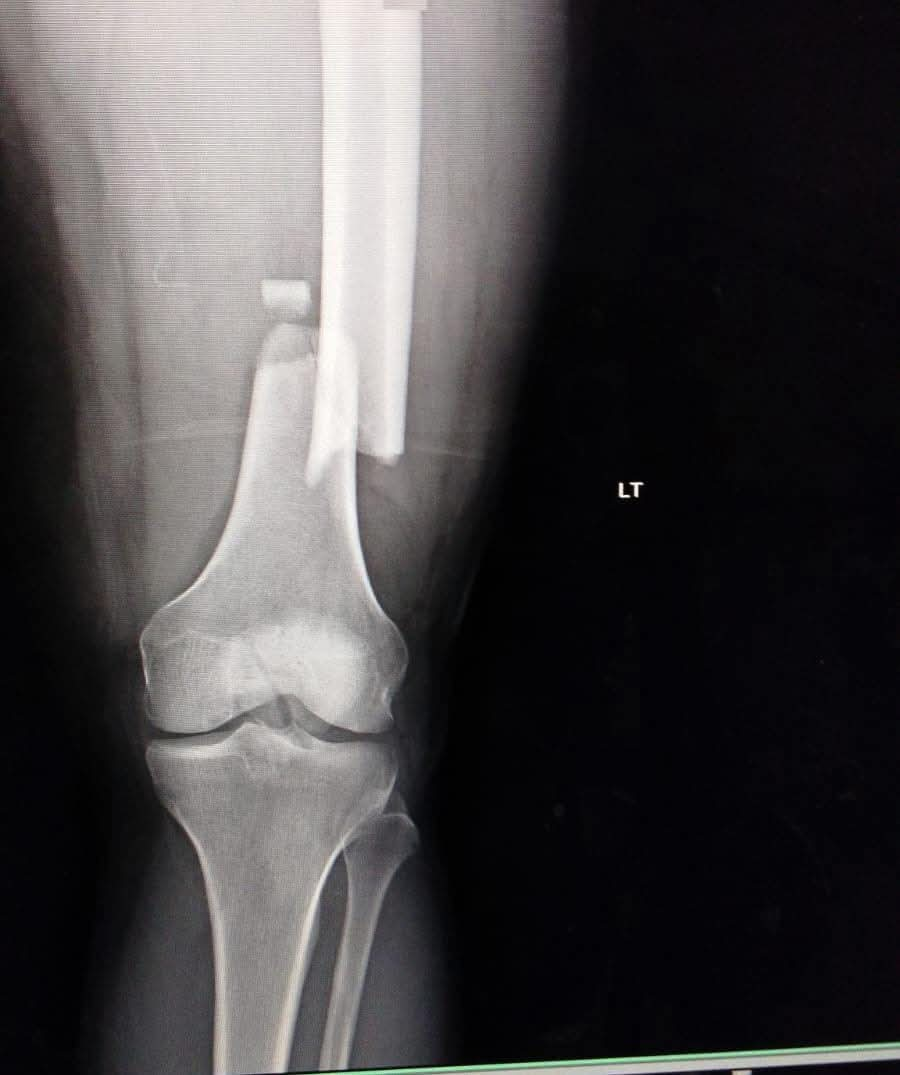

فقد استقبل قسم الطوارئ بالمستشفى المريض وهو يعاني من إصابات بالغة نتيجة الحادث. وبعد إجراء الفحوصات والأشعة الدقيقة، تبين وجود كسور متعددة شملت (عنق عظمة الفخذ، وعظمة الفخذ، وعظمة الرضفة "صابونة الركبة").

تثبيت كسر أعلى عظمة الفخذ باستخدام "مسمار نخاعي جاما" عالي الدقة.

تثبيت كسر أسفل عظمة الفخذ.

تثبيت عظمة الرضفة باستخدام مسمارين عبر فتحات جراحية صغيرة بالجلد (تدخل جراحي محدود)، مما يساهم بشكل كبير في تقليل الألم وتسريع فترة التعافي.